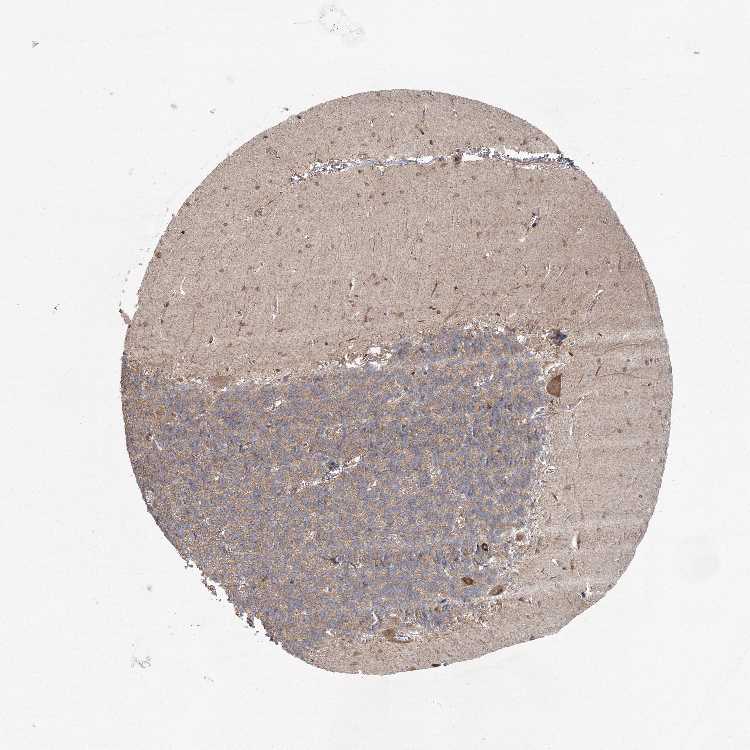

CEREBELLUM - Antibody stainingi

Antibody staining in the annotated cell types in the current human tissue is reported as not detected, low, medium, or high, based on conventional immunohistochemistry profiling in selected tissues. This score is based on the combination of the staining intensity and fraction of stained cells.

Each image is clickable and will lead to virtual microscopy that enables deeper exploration of all samples and also displays staining intensity scores, fraction scores and subcellular localization as well as patient and tissue information for each sample.

Antibody HPA038610

Purkinje cells Medium

Cells in granular layer Medium

Cells in molecular layer Medium